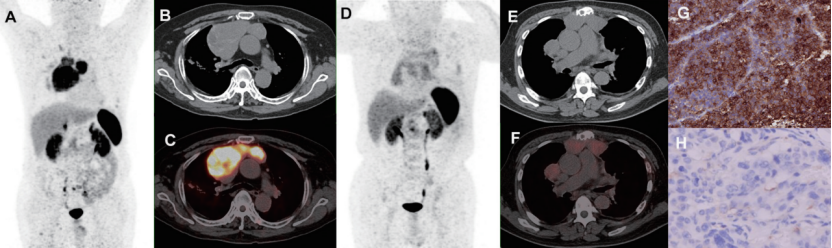

A: MIP, B: CT, C: PET/CT融合图像, 68Ga-DOTANOC PET/CT显示前纵隔类癌放射性异常浓聚, SUVmax=13.8, TBR=8.8, TLR=3.1, TSR=0.3;D: MIP, E: CT, F: PET/CT融合图像,68Ga-DOTANOC PET/CT显示前纵隔类癌轻度摄取, SUVmax=5.1, TBR=2.0, TLR=1.0, TSR=0.2; G, H: 活检病理免疫组化分别显示对应的SSTR2弥漫强阳性表达与不表达。